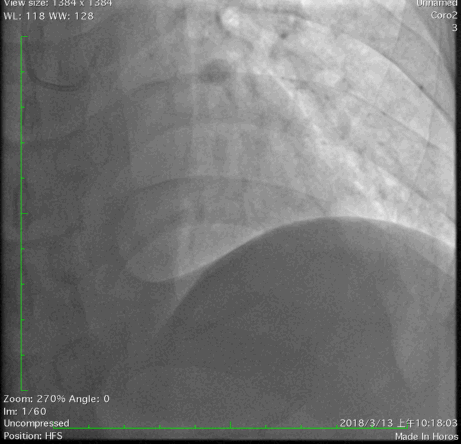

2018年3月13日外院行造影检查示左优势,LAD发出后闭塞,LCX优势型,远端可见与LAD远端形成心外膜侧支,OM1闭塞,RCA闭塞。当地尝试开通RCA和LAD失败,经我院心内、外科联合讨论后,拟心内科介入开通LAD闭塞。

冠脉造影: